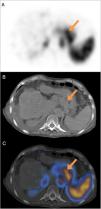

Perigastric varices detected in a gastrointestinal bleeding study with 99mTc-labeled red blood cells SPECT/CT

Varices perigástricas detectadas en un estudio de hemorragia digestiva mediante SPECT/TC con hematíes marcados con 99mTc